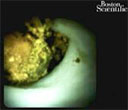

The common bile duct was accessed using a Jagtome™ RX 39 Cannulation Sphincterotome, and a balloon-occluded cholangiogram was performed (Fig. 1). The cholangiogram displayed a large filling-defect at the bifurcation, with no dye in either of the hepatics. SpyGlass™ DS Direct Visualization System was sent over the guidewire, into the common bile duct (Fig. 2). Upon arrival at the bifurcation, the area was strictured. SpyBite™ Biopsy Forceps were used to extract tissue for biopsy, and pathology confirmed a diagnosis of cholangiocarcinoma. A plastic stent was placed for further patient evaluation. The patient was found to have metastatic disease and was not a surgical candidate.

Figure 2